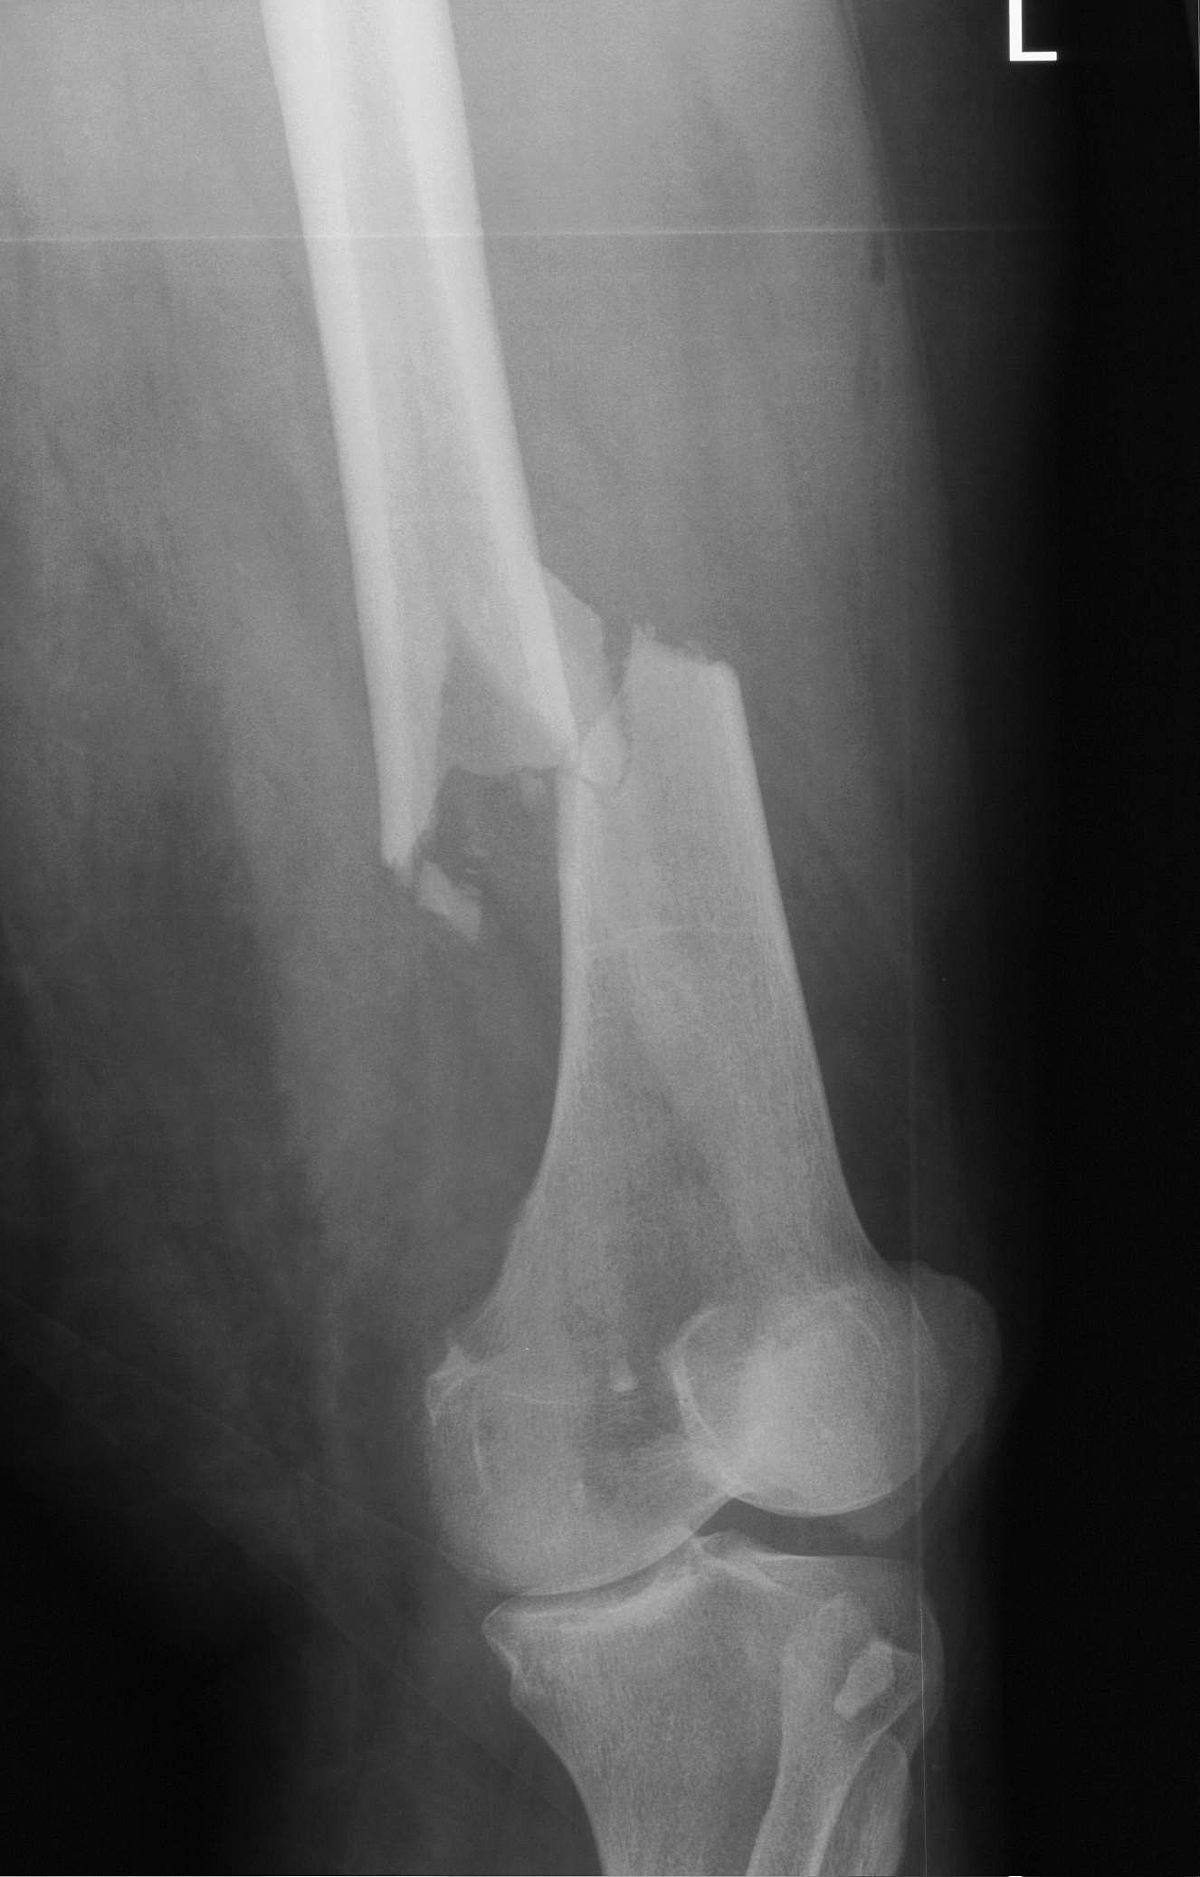

»Wir schauen uns in unserer Forschung die häufigsten Verletzungsmuster an, einzeln oder in der Summe. Häufig sind Brustkorbverletzungen, Kopfverletzungen und der Bruch von langen Röhrenknochen. Danach kommen schwere Bauchtraumata und Sepsis. Das ist wie ein Baukastensystem, das Aufschluss geben kann: Welche Konstellation ist harmlos? Und bei welchen Kombinationen muss man aufpassen, weil es dann kritisch wird? Die Brustkorbverletzung – also die Lungengewebs-Verletzung – ist einer von diesen ganz kritischen Faktoren, ebenso Gerinnungsstörungen.«